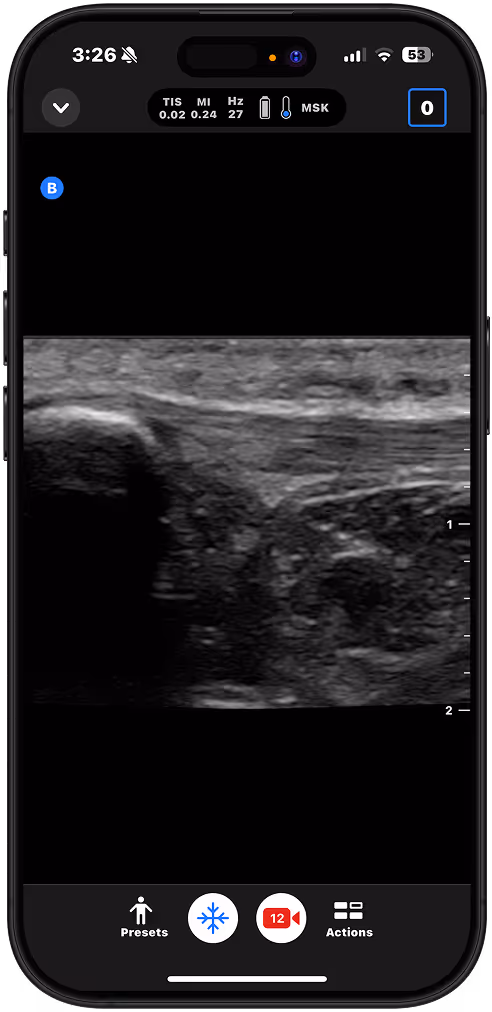

Identify joint effusions, guide aspirations, and differentiate cellulitis from abscess.

Patellar Tendon